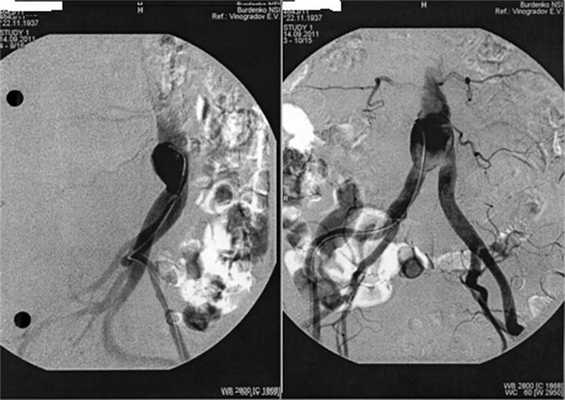

Физикальное обследование пациента не выявило признаков поражения аорты. В связи с подозрением на аневризму проведена аортография, подтвердившая предположение о формировании аневризмы аорты на уровне разрушенного позвонка LIV(рис. 2). Рисунок 2. Контрастная аортография -—прямая (слева) и боковая проекция. Определяется аневризматическое расширение аорты на уровне бифуркации. Экстравазального выхода контрастного вещества не отмечено.